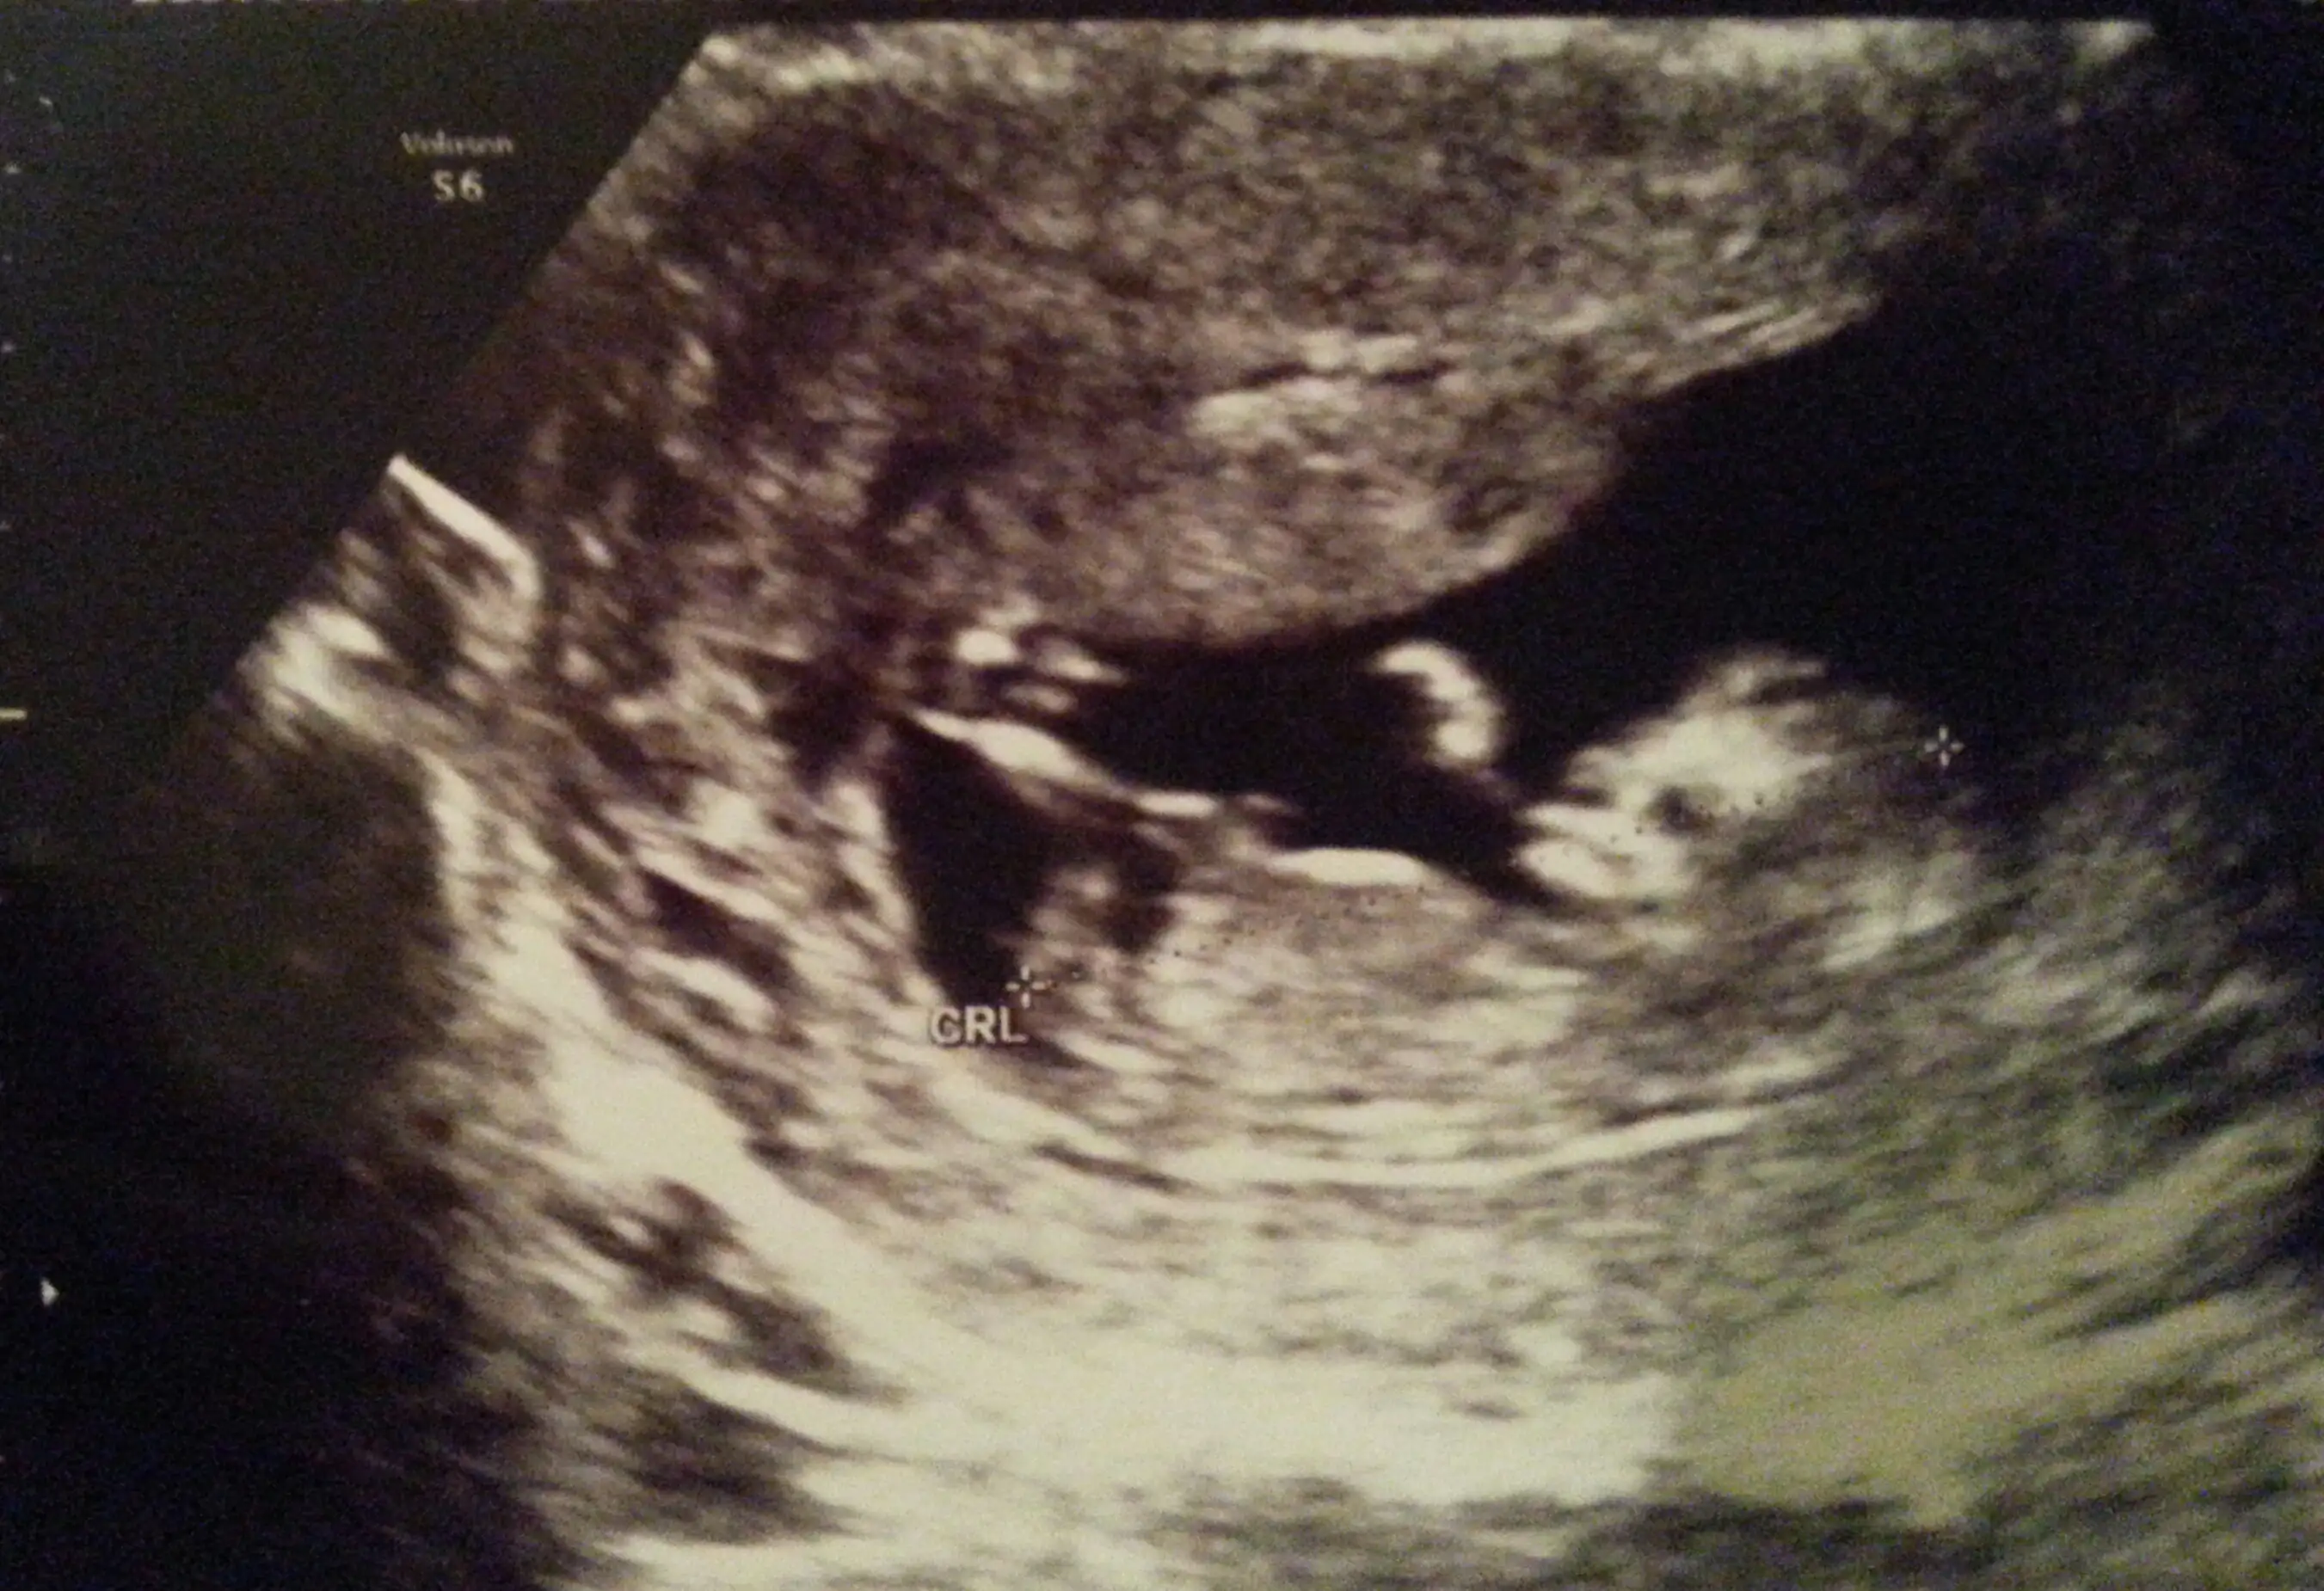

İlk iki görüntü ense kalınlığına bakmak için girdiğim ultrason görüntüleri alttaki diğer 2 görüntüyse normal doktor kontrolündeki ultrason görüntüleri ve ikisi de aynı gün ve tam 12 haftalıkken ve tekrar teşekkür ediyorum